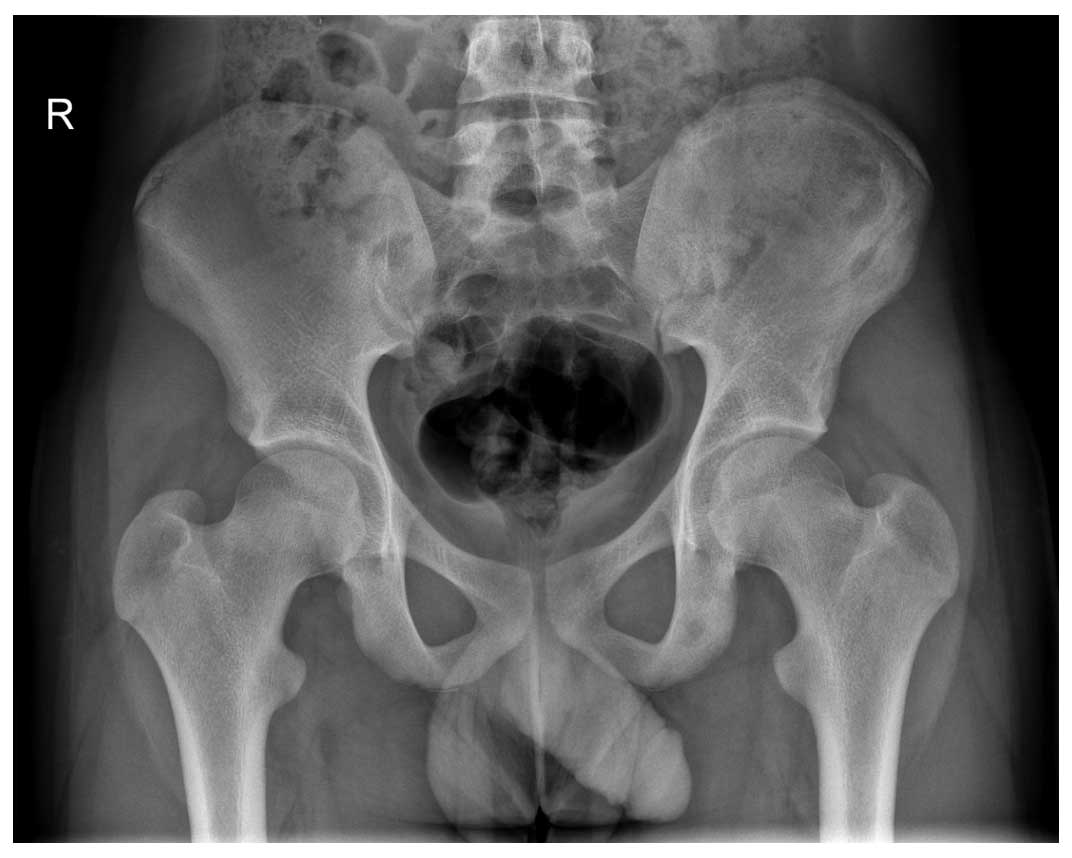

Ameliyat Öncesi: Sol iliak kanat üzerinde düzensizlik görülmekte.

Ameliyat Sonrası: İnternal hemipelvektomi sonrası girdlestone işlemi görülmekte.